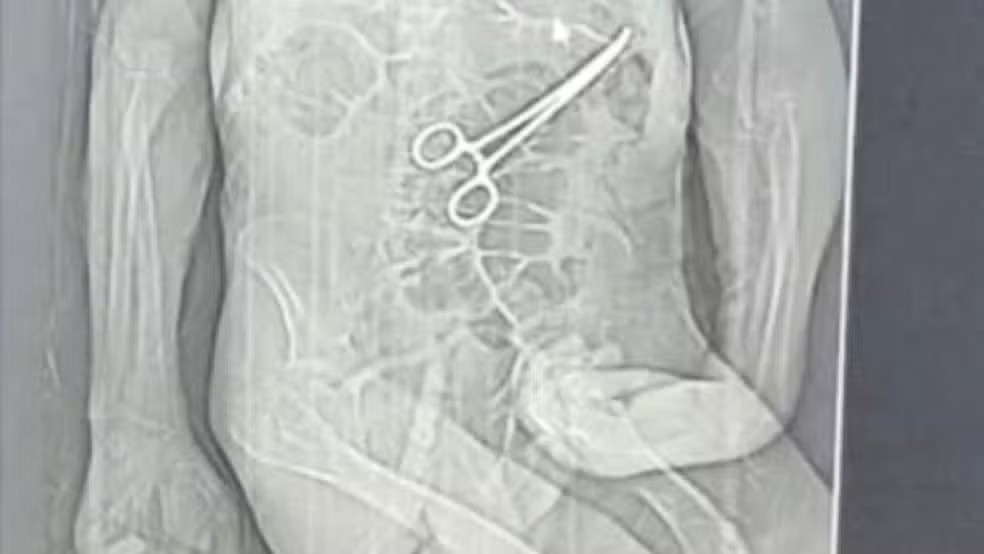

Segundo o advogado da família do idoso, as medidas legais começaram a ser adotadas depois que um exame de tomografia, divulgado por uma rádio local, chegou ao conhecimento de parentes. A imagem indicaria a presença do instrumento cirúrgico no corpo do paciente.

De acordo com a família, a pinça cirúrgica foi esquecida dentro do corpo do paciente após a primeira cirurgia, fato que, segundo os familiares, só veio à tona depois do óbito. Manoel Cardoso de Brito morreu no dia 24 de dezembro.